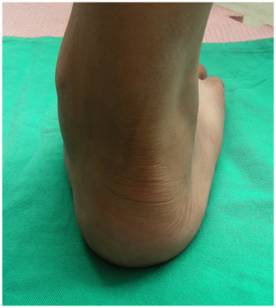

体格检查 详细而全面的体格检查,是评价扁平足畸形的严重程度;是否发生合并症;以及是否伴有关节退行性改变最基本的诊断方法。扁平足畸形通常表现为跟骨外翻,前足的内翻以及外展,有时会合并距下关节半脱位。临床检查通常以坐位、立位和行走时检查最为重要。 |

跟骨外翻角 – 患者站立位,取跟腱轴线以及跟骨轴线为角的两条边,取距骨结节位置为角的顶点,测量跟骨外翻角。 |